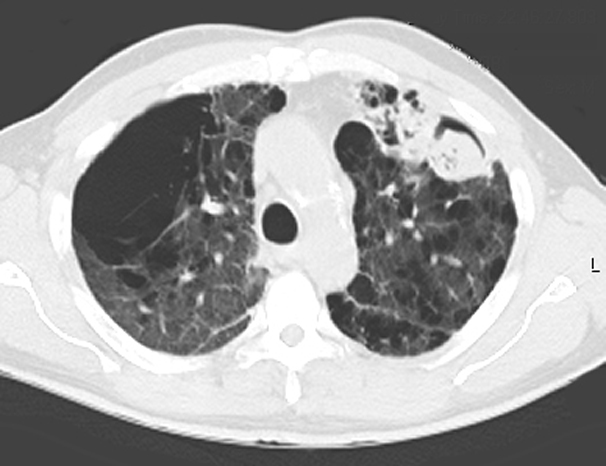

The definitive treatment of symptomatic aspergilloma is surgical resection. Patients with aspergilloma who present with hemoptysis are at risk of death due to massive hemoptysis and/or respiratory insufficiency caused by aspirated blood. Catheter embolization of bronchial arteries can be used to control acute bleeding (Figure 1), but is not durable. Likewise, intracavitary instillation of antifungal agents has mixed outcomes and seldom results in complete resolution of the cavity (Figure 2 ) 1. Systemic antifungal agents play little role as primary treatment because they do not penetrate the aspergilloma cavity 2. Resection in appropriate patients provides a definitive diagnosis and a durable treatment response.

Unfortunately, most patients with aspergilloma have significant underlying pulmonary disease and are at increased risk for resection. An aspergilloma in the setting of underlying pulmonary disease is referred to as a complex aspergilloma (Figure 3). Associated pulmonary diseases in our practice have included bronchiectasis, sarcoidosis, COPD, lung abscess, rheumatoid lung disease, tuberculosis, and complications of systemic immunosuppression.